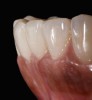

A resorbable membrane sutured around the teeth bordering the intrabony defect.

Figure 15